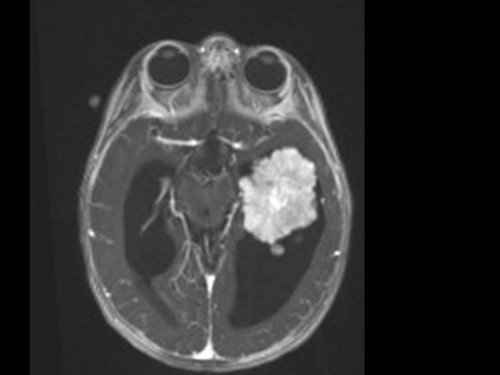

10 Monate altes Mädchen. Der Kinderarzt stellt fest, dass das kleine Mädchen einen recht großen Kopfumfang hat, nicht mit den Augen fixiert und anscheinend auch nicht richtig sehen kann. Damit bestätigt er die größten Befürchtungen der Eltern, denen in den letzten Wochen aufgefallen war, dass ihre Tochter nach keinem Spielzeug mehr greift und sie nur dann anlächelt, wenn sie zu ihr sprechen.

Bildgebung - MRT